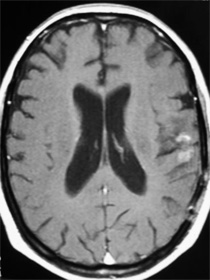

RNM de control a 3 meses. Observe la marcada reducción tumoral y desaparición del edema y del efecto de masa.

A las pocas semanas de la reintervención. Paciente logra caminar y ser independiente revirtió el déficit neurológico con sobrevida funcional de 8 meses de excelente calidad de vida.